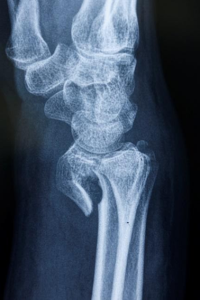

Doktor tanıyı doğrulamak için el ve bilek radyolojik taramaları isteyecektir. En popüler ve yaygın olarak kullanılan tanısal görüntüleme yöntemi X ışınlarıdır. X ışınları, kemiklerin gerçekten kırılıp kırılmadığını ve bunların yer değiştirmiş kırıklar olup olmadığını ortaya çıkarabilir . Ayrıca kaç tane kırık kemiğin mevcut olduğunu da gösterebilirler.